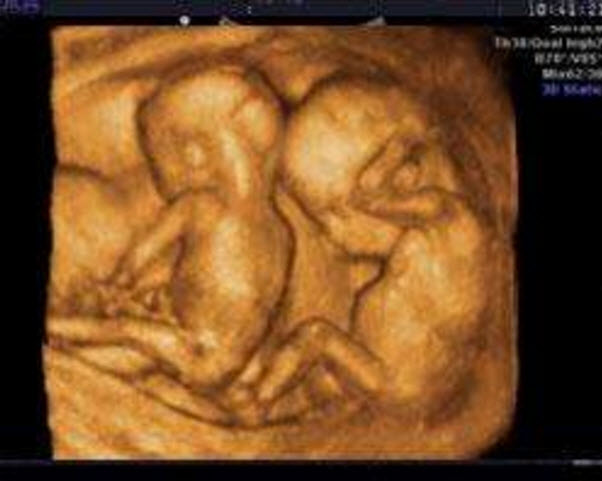

超聲波檢查檢測(cè)到兩個(gè)胎心波

超聲波檢查檢測(cè)到兩個(gè)胎心波是最明顯的懷雙胞胎的癥狀。如果懷了雙胞胎,那么用超聲波檢查就可測(cè)到兩個(gè)不同速度的胎心波,同時(shí)用X線檢查也會(huì)顯示兩個(gè)胎兒的骨骼。